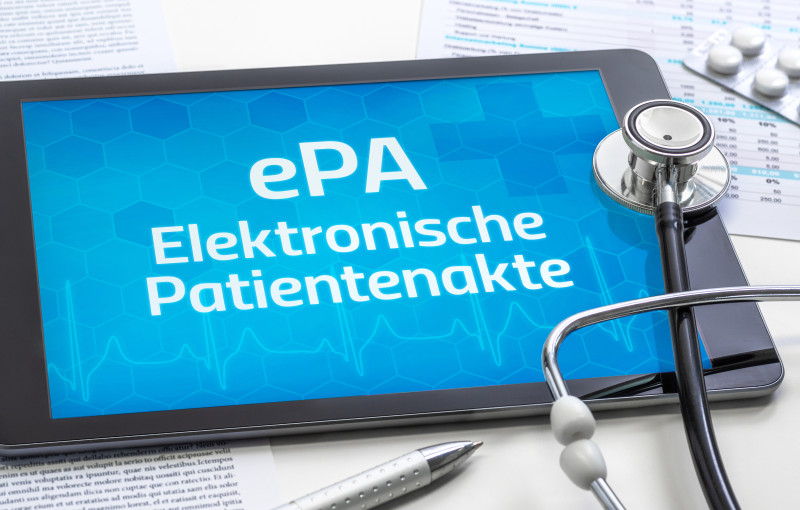

Andrea Gaitanides_adobe_842020584.jpg)